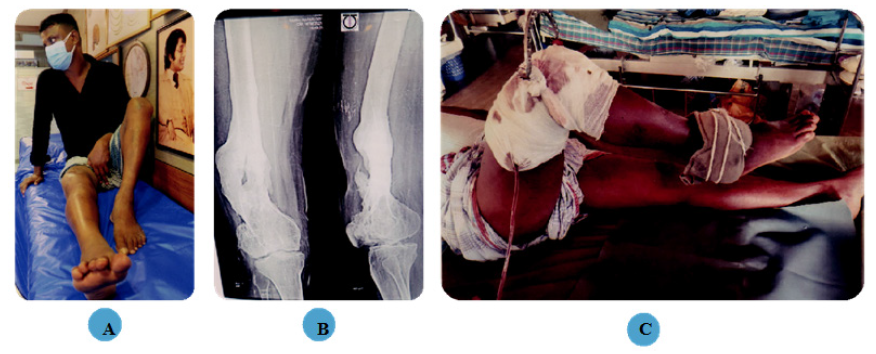

Figure 2 38 years old man, Right knee extension contracture.

(A) Patient with right knee extension contracture before surgery.

(B) Radiograph of right knee extension contracture before surgery.

(C) Patella traction and 1.5kg ankle weight.